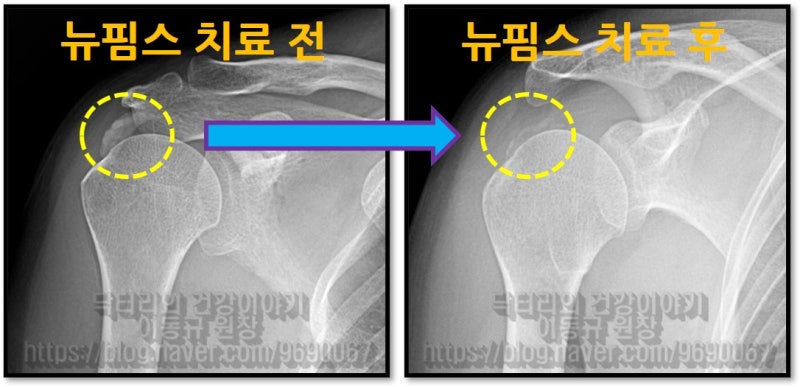

58세 여자 환자분으로 6개월 간 어깨 통증으로 고생을 하신 분입니다. 타병원에서 수차례 주사치료를 받았지만 증상의 호전이 없고 통증이 더 심해지고 가동범위 제한까지 오셨던 분이었습니다. 타병원에서는 수술적 치료를 권유받으셨다고 합니다. 석회성 건염 진단을 받으신 상태로 X-ray 를 확인해 보겠습니다.

이렇게 석회를 분쇄해서 흡입을 하게 되고 뉴핌스치료(석회분쇄흡입술) 후 찍은 X-ray를 보면

시술 후 통증이 확연하게 감소 되었고 환자는 아주 만족해 하셨습니다. 아직 남아있는 석회에 대해서는 추가적인 충격파 치료를 통해 치료를 하면 됩니다. 어깨 석회성 건염은 수술 없이 나을 수 있는 질환입니다. 물론 회전근개 파열이 동반되어 있다면 파열의 양상에 따라서는 다르겠지만 수술이 필요할 수도 있습니다. 하지만 석회성 건염만 있다면 수술을 필요치 않다고 생각합니다.